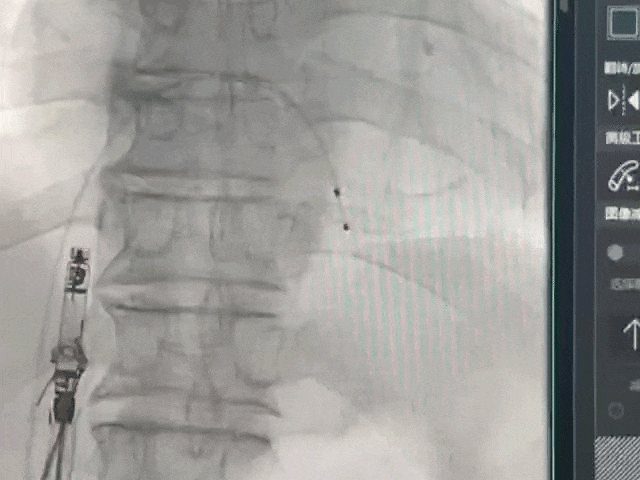

手术过程部分展示

轻微释放调弯精确调整位置

右前30°造影,位置理想

左前45°造影贴靠间隔